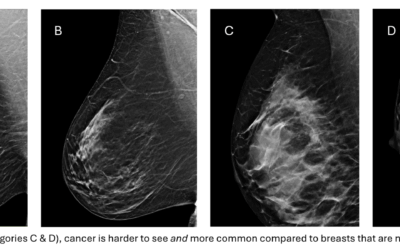

What Are Dense Breasts And Why Do They Matter?

There is a lot of confusion about what dense breasts are and why they matter so much. When a primary care doctor does a physical exam and tells a patient that her breasts are dense, they mean that they feel dense. But on a mammogram, we’re not asking if the breasts...